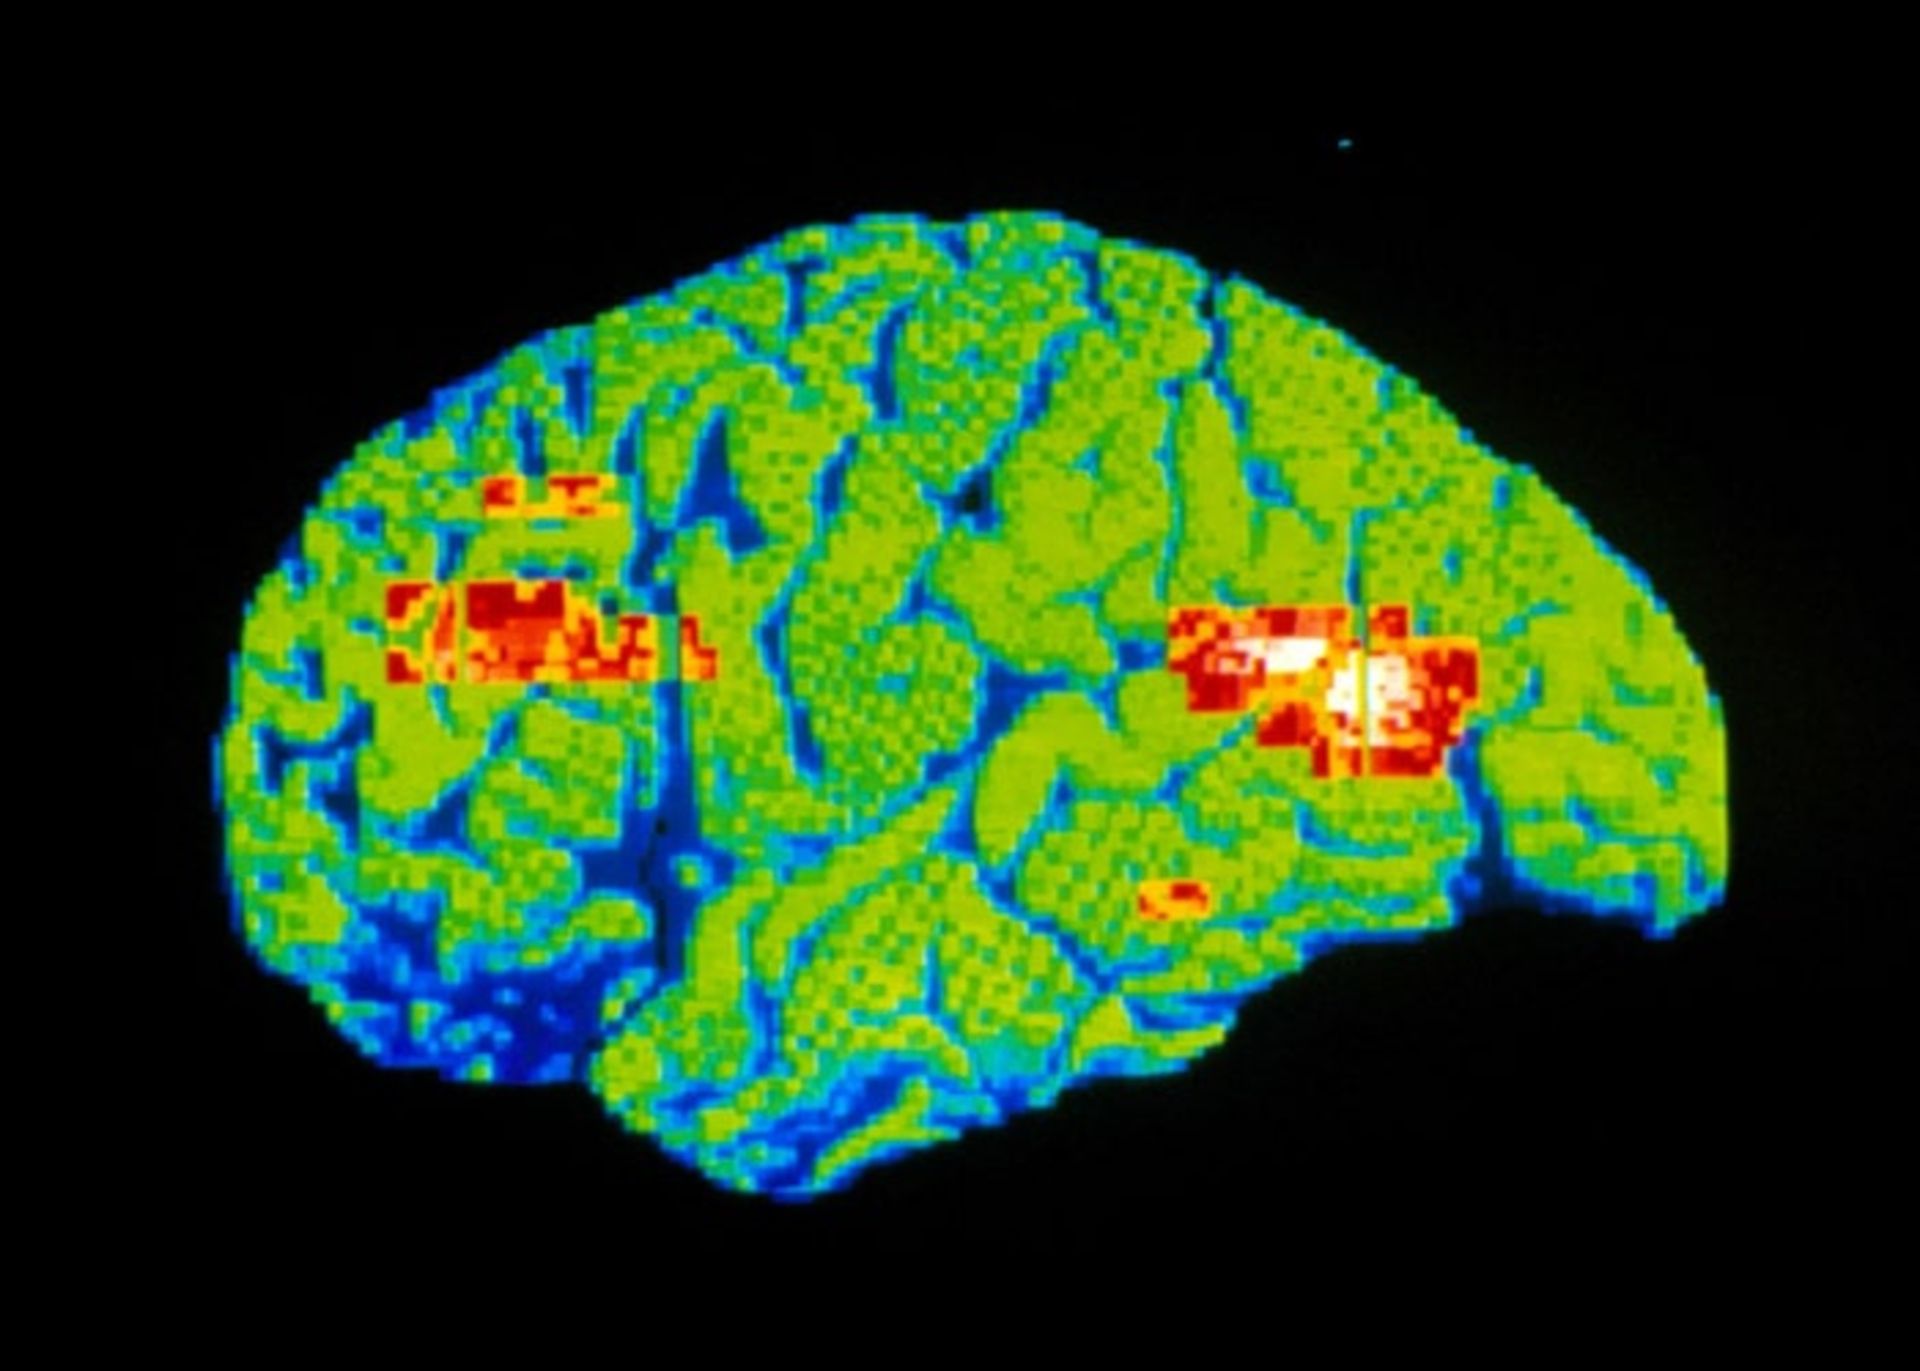

پت اسکن رنگی مغز

پت‌اسکن رنگی مغز یک فرد افسرده که در آن مناطقی از مغز که در آن جریان خون و فعالیت متابولیکی به‌طور غیرعادی پایین است، به رنگ قرمز نشان داده شده است